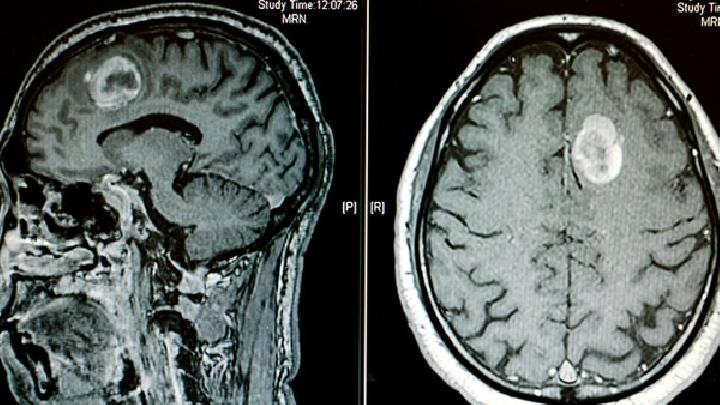

1.下丘脑综合征(HYPOTHALAMUS SYNDROME,HTS) 内分泌代谢功能障碍的临床特征,伴有自主神经功能障碍。其病因与临床表现有很大差异。临床症状和体征不能用单垂体或单靶腺体的损伤或其他原因来解释。因此,应结合具体症状和检查结果进行识别。